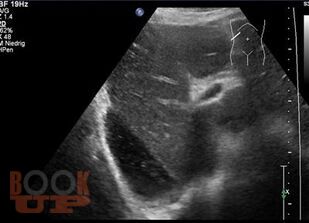

В учебном пособии рассматриваются вопросы этиологии, патогенеза, классификации, клиники, принципов диагностики и лечения, профилактики как специфических (перитонит, кишечная непроходимость, кровотечение, абдоминальный компартмент-синдром), так и неспецифических (тромбоэмболия, эндогенная интоксикация, патология дыхательной и сердечно-сосудистой систем) осложнений, развивающихся после хирургических вмешательств на органах брюшной полости.